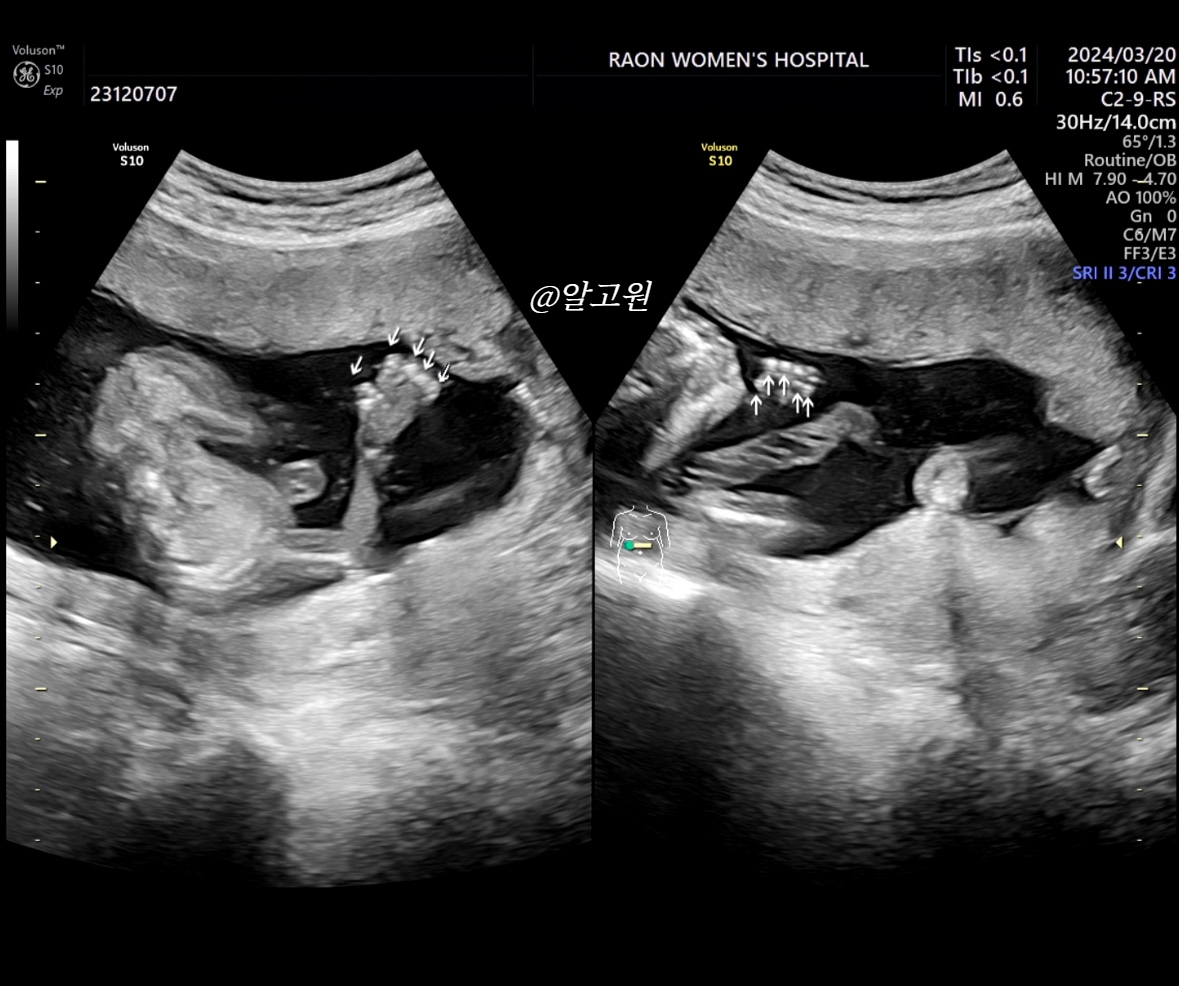

4. 손가락 & 발가락 확인

- 오른쪽, 왼쪽 손가락과 발가락이 5개씩 잘 있는지

초음파로 봐주셨는데요.

직접 화살표 표시 해주셔서 보기 쉬웠어요!

너무 깜찍한 손가락과 발가락ㅋㅋ( ˃᷄˶˶̫˶˂᷅ ) 💗